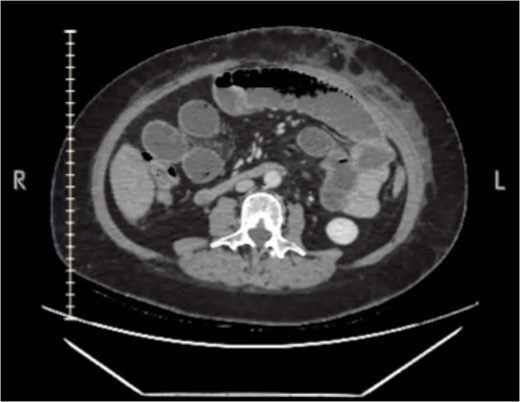

Laboratory tests indicated leukocytosis (13.4 × 103/μL) with neutrophilia (89.6%). A contrast-enhanced computed tomography (CT) scan demonstrated small bowel dilation up to the posterior distal suture (Fig. 1), mild right pleural effusion, and minimal free gas in the mediastinum. These findings suggested a small bowel obstruction, prompting an emergency diagnostic laparoscopy.